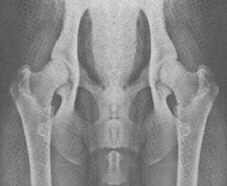

Links HD A, rechts HD E

Foto: Mit freundlicher Genehmigung des Schweizer Do-khyi Clubs